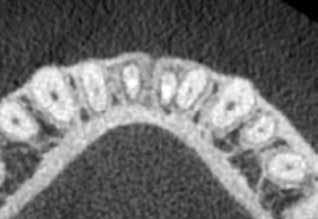

A 28 éves hölgy pácienst az eddig fel nem lelt második mesio-bukkális (MB2) gyökércsatorna lokalizálása és a kérdéses fog endodonciai ellátása miatt utalták dr. Karaś rendelőjébe. A fog panaszos volt (jobb felső első nagyőrlő; 16) és kezelést igényelt. A mesialis gyökércsatorna vizsgálata, valamint a kezelés megtervezése céljából CBCT-felvétel készült. A gyökér alakja és a gyökérhártyarés kiszélesedése alapján különálló gyökércsatorna bemeneti nyílást és önálló foramen apicale-t vélelmeztünk az MB2 csatorna számára. Egy axiális irányú szeleten a mesio bukkális gyökér palatinális részén egy keskeny önálló csatornaszakaszt észleltünk, amely tovább erősítette az önálló MB2 csatorna fennállásának valószínűségét. Gyulladásra utaló jeleket észleltünk a mesio-, és diszto-bukkális gyökerek gyökércsúcsánál, valamint az azonos oldali arcüregben (1. a–c ábra).

A mesialis gyökér megfelelő endodonciai ellátásának ellen őrzése céljából a pácienst egy kontroll CBCT-felvételre irányítottuk. A felvételen látható volt, hogy az MB2 csatornát teljes terjedelmében ki tudtuk tölteni a sealerrel, továbbá, hogy az apikális harmadban az MB1 és MB2 csatornák között egy keskeny összeköttetés található, valamint hogy az MB1 és MB2 gyökércsatorna különálló végződéssel rendelkezik (14. ábra) . A fogat kompozitfelépítéssel láttuk el, majd visszairányítottuk a beküldő orvosához. Csücsökborítást biztosító indirekt restaurátum készítését javasoltuk, illetve 6 hónap múlva kontrollvizsgálat céljából visszarendeltük magunkhoz. A 6 hónapos kontroll során készített CBCT-felvételen a gyökércsúcsok körül nem voltak gyulladásra utaló jelek. A fog teljesen panaszmentes volt és a Schneider membrán megvastagodását sem észleltük (15. a–b ábra.).